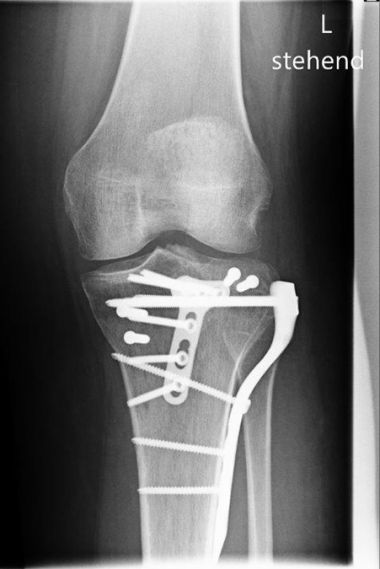

Bild Patientin 3 Monate nach Tibiakopffraktur

„Ich bin an einem Sonntag mit meinem Fahrrad gestürzt und dachte zuerst gar nicht, dass das so schlimm gewesen ist. Der Schienenbeinkopf war jedoch auf der Außenseite gebrochen und die Gelenkfläche richtig eingedrückt. Das konnte man auf den CT- Bildern gut sehen. Nach der Operation habe ich dann eine ganze Zeit entlastet aber schon bewegt. Jetzt 3 Monate nach der Verletzung geht es eigentlich schon ganz gut.“

Im April 2022 versorgter außenseitiger Schienenbeinkopfbruch (Tibiakopffraktur) bei einer 35-jährigen Patientin. Bei der Versorgung wurde anhand der CT – Untersuchung die außenseitige kniekehlenwärts gelegene Gelenkflächenabsenkung wieder angehoben und mit Knochen unterfüttert. Intraoperativ wurde mit Hilfe der Arthroskopie die Gelenkfläche überprüft. Anschließend wurde die Rekonstruktion durch die seitliche und hintere Platte sowie zusätzliche Schrauben stabilisiert. Nach der Operation konnte das Knie steigernd bewegt und zunächst mit einer Teilbelastung an Unterarmgehstützen belastet werden. Nach 3 Monaten ist die freie Belastung bei guter Beweglichkeit wieder erzielt worden.